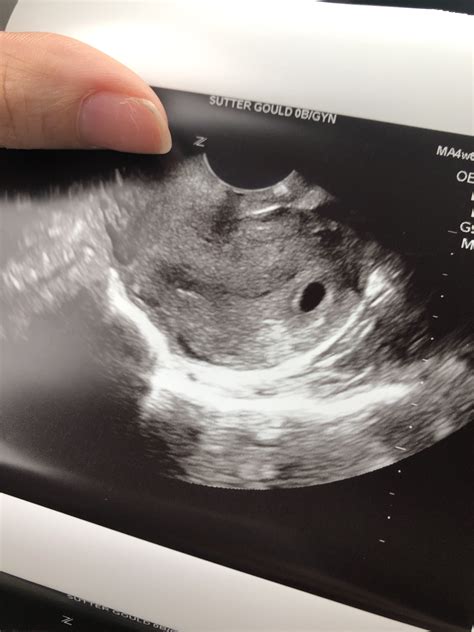

• Gestational Sac: This is the first structure visible on the ultrasound, appearing as a small, fluid-filled sac within the uterus.

• Yolk Sac: As the gestational sac develops, a yolk sac will form within it. This sac provides essential nutrients to the embryo before the placenta takes over.

• Embryo: At 4 weeks, the embryo itself is very small, often measuring less than 1 mm. It may not be visible on the ultrasound, but the presence of the gestational and yolk sacs is a positive sign.

If the ultrasound is performed too early, it might be difficult to detect these structures clearly. In such cases, a follow-up ultrasound may be scheduled to confirm the pregnancy.

• Positive Results: The presence of a gestational sac and yolk sac indicates a viable pregnancy. The healthcare provider will discuss the next steps, including scheduling future ultrasounds and prenatal appointments.

• Inconclusive Results: If the structures are not clearly visible, a follow-up ultrasound may be recommended to confirm the pregnancy.